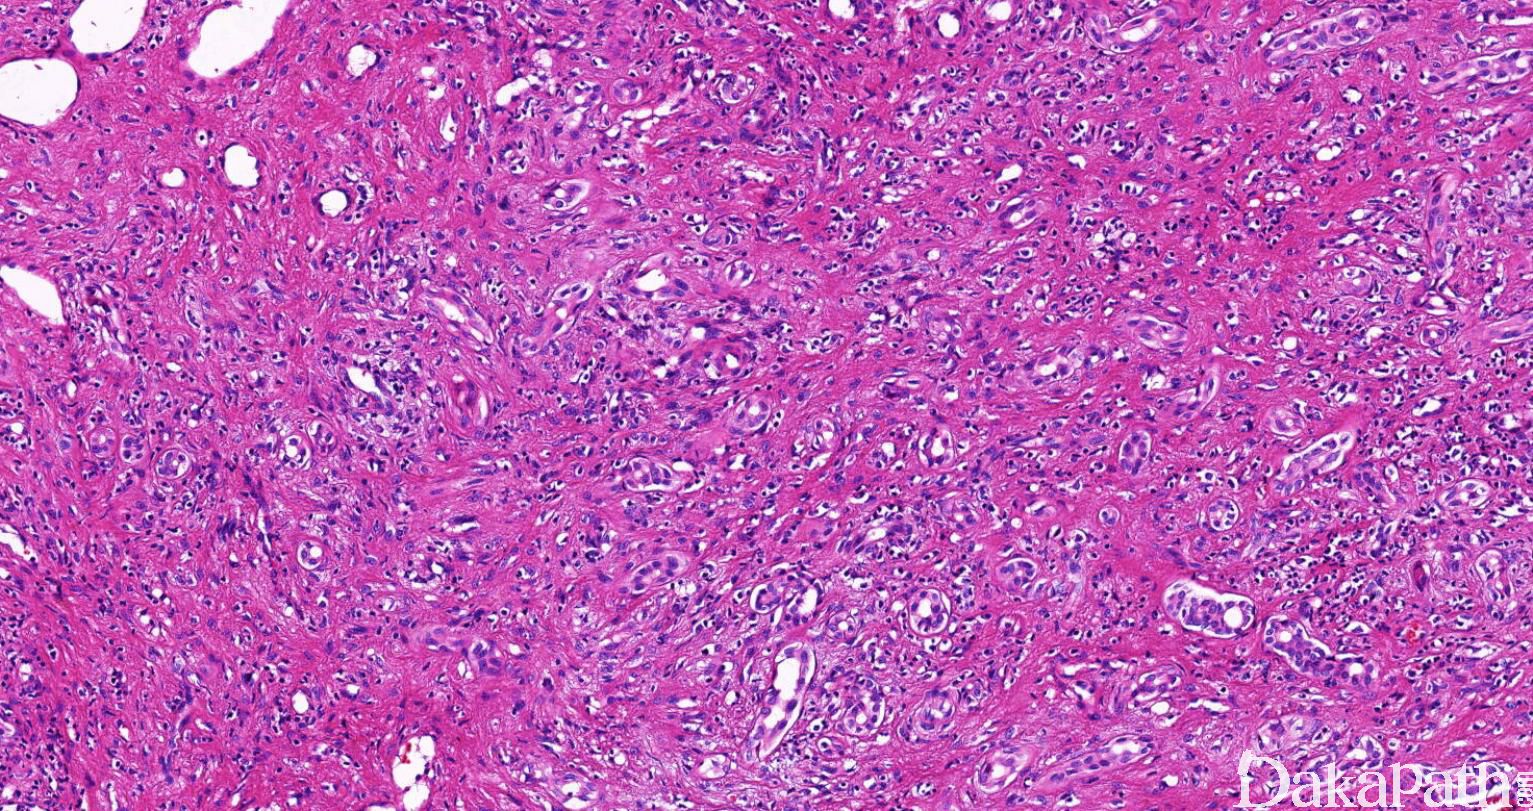

大多数 ICC 呈大小不一的管状生长方式,少数呈乳头状、腺泡状或条索状结构;

肿瘤细胞常小至中等大小,立方或柱状,可具多形性,胞质淡染,弱嗜酸或空泡状,有时胞浆丰富透亮,或类似于杯状细胞;细胞核较小,可见核仁;

间质不同程度纤维化、通常肿瘤中心部位硬化明显并玻璃样变,细胞密度低;

肿瘤常沿肝窦浸润,或直接替代邻近肝索上的肝细胞;

常浸润汇管区,并浸润小叶间脉管;

根据其形态学分为高分化、中分化和低分化腺癌,大多数为高分化管状腺癌,伴或不伴微乳头结构;中分化腺癌由中度变形的融合成筛状的腺管或条索状结构组成,而低分化癌的变形的腺管或条索状结构具有显著的细胞多形性;